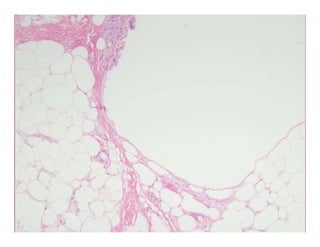

LipodermatosclerosisLipodermatosclerosisLipodermatosclerosisLipodermatosclerosis

Synonyms:Synonyms:Synonyms:Synonyms:

–– Membranous lipodystrophyMembranous lipodystrophy

–– Sclerosing PanniculitisSclerosing Panniculitisgg

Histology:Histology:

–– Stasis changes at topStasis changes at top

–– Septal fibrosisSeptal fibrosis –– THICK septaTHICK septa

–– Fatty microcysts with “membranocystic change”Fatty microcysts with “membranocystic change”

Feathery cuticle inside cystFeathery cuticle inside cyst –– “arabesque pattern”“arabesque pattern”

LipodermatosclerosisLipodermatosclerosisLipodermatosclerosisLipodermatosclerosis Synonyms:Synonyms:Synonyms:Synonyms: –– Membranous lipodystrophyMembranouslipodystrophy –– Sclerosing PanniculitisSclerosing Panniculitisgg Histology:Histology: –– Stasis changes at topStasis changes at top –– Septal fibrosisSeptal fibrosis –– THICK septaTHICK septa –– Fatty microcysts with “membranocystic change”Fatty microcysts with “membranocystic change” Feathery cuticle inside cystFeathery cuticle inside cyst –– “arabesque pattern”“arabesque pattern”